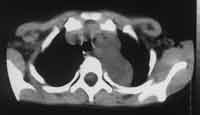

Рис. 2. Ганглионеврома верхнего средостения у больной С., 10 лет.

(а) Нативное КТ-иследование, сосудистые элементы не дифференцируются в опухоли.

(б) КТА артерий дуги аорты. Левая подключичная артерия расположена в толще опухоли, левая общая сонная артерия оттеснена кпереди.